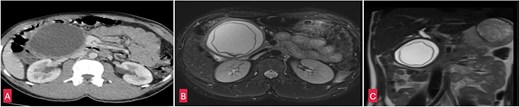

Blood tests were unremarkable and serum amylase (103 U/L) and lipase (165 U/L) were within normal limits ruling out acute pancreatitis. An abdominal ultrasound identified a cystic lesion in the head of the pancreas measuring 7 × 8 cm. Contrast enhanced computed tomography (CECT) whole abdomen revealed a unilocular, thick walled, hypodense cyst (7.5 × 8.2 × 10 cm) near the head and uncinate process of pancreas. The cyst displaced the antrum of the stomach, transverse colon, first and second part of the duodenum, suggestive of a pancreatic pseudocyst. However, the absence of trauma or pancreatitis made this diagnosis unlikely. MRI whole abdomen revealed a well defined, thick walled cyst with a characteristic undulating membrane suggesting hydatid cyst (Fig. 2). Echinococcal serology was positive, with IgG (16 U/ml) and IgM (20 U/ml) confirming the diagnosis of hydatid cyst.

(A) Coronal section of CECT abdomen showing a thick walled, well defined round to oval cystic lesion ~7.5 × 8 × 10 cm in the head and uncinate process of pancreas. (B) Coronal section of MRI-magnetic retrograde cholangio-pancreatography (MRCP) abdomen showing a well defined thick walled cystic lesion in the head and uncinate process of the pancreas with undulating membrane noted within the cyst. (C) Saggital section of MRI-MRCP abdomen with similar findings as above.